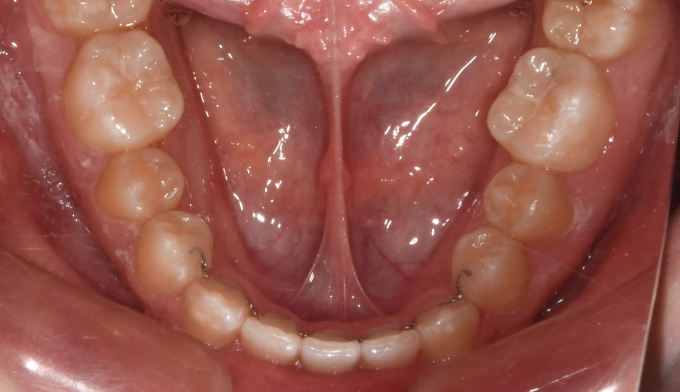

아래 앞니 하나가 선천적으로 부족한 경우이지만 주걱턱 경향으로 인해 아랫니가 윗니를 계속 자극하여 윗니까지 벌어진 케이스입니다. 윗니의 공간을 닫아주기 위하여 아래앞니를 먼저 후방이동시켜줬고, 이후에 벌어진 윗 앞니를 가지런하게 모아 마무리하였습니다. 아래앞니 하나가 부족하기때문에 위아래 가운데선을 맞추지 않고 종료하였습니다. 총 교정기간은 11개월입니다.